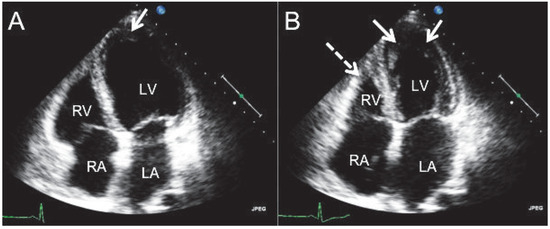

Churg-Strauss Syndrome

by Sina Lautwein, Frank Enseleit, Urs Schwarz and Thomas F. Lüscher

A 62-year-old patient was admitted to our hospital because of severe fatigue, headache, arthralgias, myalgias and an unsteady gait. She presented with a reduced general condition and splinter haemorrhages of the fingers. Due to a known history of asthma, signs of eosinophilia, sinusitis, [...] Read more.

A 62-year-old patient was admitted to our hospital because of severe fatigue, headache, arthralgias, myalgias and an unsteady gait. She presented with a reduced general condition and splinter haemorrhages of the fingers. Due to a known history of asthma, signs of eosinophilia, sinusitis, endomyocardial thrombotic apposition in both chambers and neurological deterioration, the diagnosis of multisystem vasculitis (ChurgStrauss syndrome) was made. The symptoms resolved after steroid therapy. Churg-Strauss syndrome is a rare necrotising systemic inflammatory vasculitis of the small and medium-size vessels. Typically, the disease has three distinct stages, which can possibly involve several organic systems (e.g., pulmonary, cardial, renal and nervous system). The treatment for ChurgStrauss syndrome includes steroids and/or other immunosuppressive drugs. After introduction of steroid therapy, the prognosis of the disease improves significantly, but heart failure remains as a major determinant of mortality. Full article